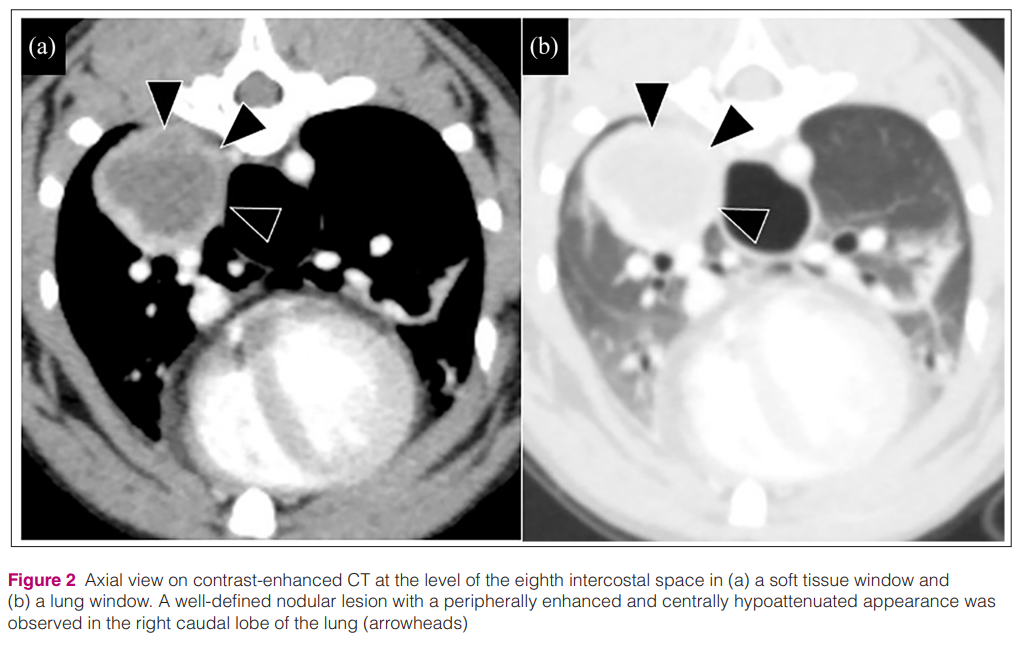

폐 종양이 잘 발생하는 우측 폐 후엽부 종괴성 병변이 있었는데

CT 촬영을 해보니

조영상에서 낭성 구조를 가지고 있어서 폐종양의 가능성은 낮아졌지만 실제 무엇인지 알기 위해 FNA를 CT 가이드로 했다는 것.

결국 독성변화가 있는 염증세포와 다량의 세균, 탐식된 세균 등이 보여 농양으로 진단하고

강한 항생요법으로 치료했다는 증례이다.